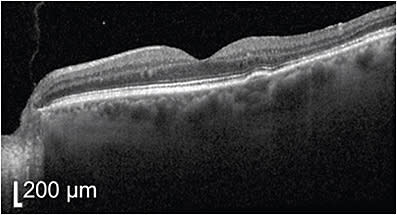

A 47-year-old male physician presented initially with a 2-week history of metamorphopsia in the left eye. After 6 months of observation, which did show some initial improvement in central subfield thickness and volume, the improvement stalled despite stress reduction and a 1-month trial of eplenerone. At month 6, progressive retinal pigment epithelium (RPE) atrophy was noted (Figure 1), and the decision was made to undergo half fluence photodynamic therapy with verteporfin. An area of 2800 µm was treated (total area of RPE changes) with 15 mg of verteporfin.